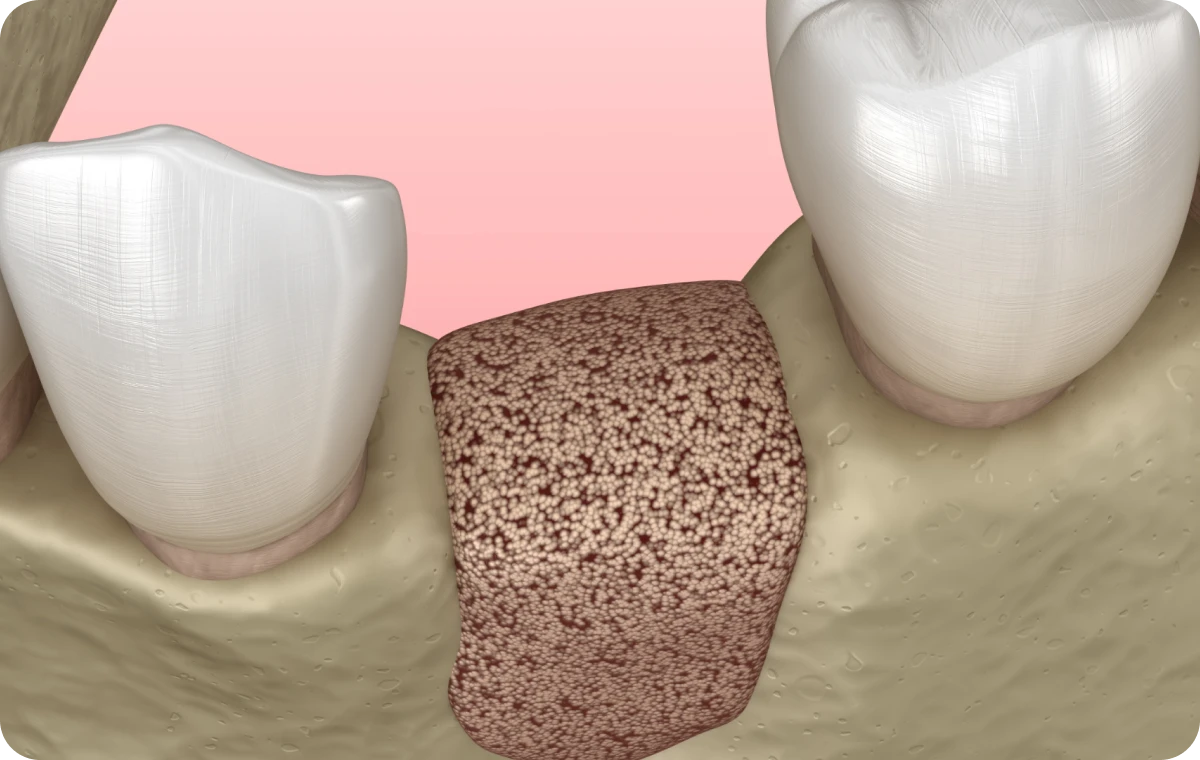

La chirurgie orale regroupe l’ensemble des interventions chirurgicales pratiquées au niveau de la bouche, des dents et des mâchoires. Elle peut inclure des extractions dentaires complexes (comme les dents de sagesse), la gestion de kystes ou de lésions buccales, ainsi que des chirurgies correctrices visant à améliorer la santé et la fonctionnalité de la sphère orale. Ces actes sont réalisés sous anesthésie locale, et dans certains cas sous anesthésie générale, afin d’assurer confort et sécurité aux patients.

Création d’un plan de traitement sur-mesure à l’aide de nos outils : planification esthétique ou implantaire et définition de l’objectif thérapeutique.